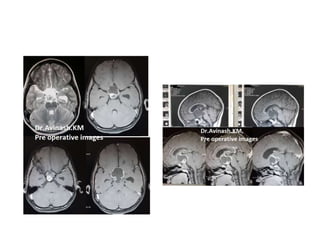

FIGURE 4. The capsule of the cystic craniopharyngioma was firmly attached to the left

hypothalamus, the stalk was dislocated to the right side (Patient 6). The outgrowth of the

craniopharyngioma from proximal stalk is recognizable A. Complete removal of the capsule was

possible, but produced subpial blood injection over the left hypothalamic surface B. MRI scan

revealed a small ischemic injury in the left hypothalamus C. This patient had transient sleep

disorder, moderate hyperphagia and memory problems (see also a supplemented video

material 1).

FIGURE 2. In this cystic craniopharyngioma (Patient 5), the stalk was centrally

infiltrated close to the pituitary and could not be preserved A. The incipient third

ventricle entrance is seen from intracavitary view. The slit into the third ventricle is

still covered with tumour capsule B. Complete removal of the capsule opened the

third ventricle C. Petehiae in the hypothalamus bilaterally resulted from apparently

gentle traction and blunt dissection of the capsule away from the hypothalamus

D. Psychoorganic change, disorientation and memory deficits were noticed in less

than a week after surgery, the transient sleep disorder become apparent in the

second week postoperatively (see also a supplemented video material 2).

FIGURE 3. Large craniopharyngioma (Patient 3) produced unilateral hydrocephalus

by obstructing the right formen of Monro A. The dome was filled with soft

cholesterine cristals B, which were easily removed. Lower limbus of the right foramen

of Monro is seen through the empty third ventricle D. Despite bilateral preservation

of anteromedial hypothalamus C and stalk preservation E, the patient developed

panhypopituitarism and diabetes insipidus with long lasting psychoorganic change